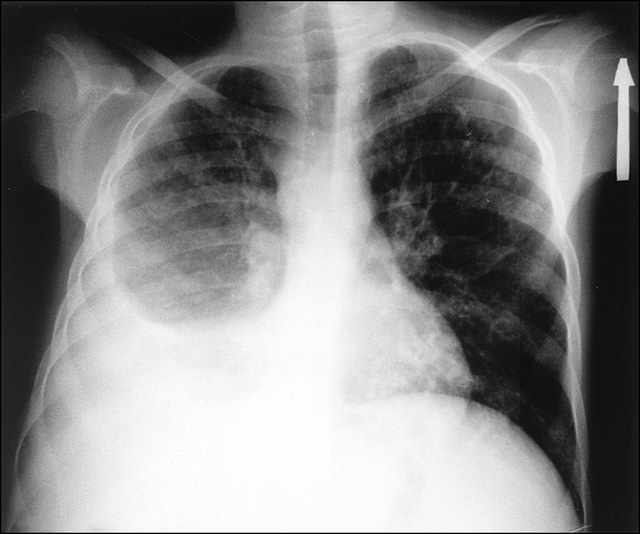

Nếu bệnh xảy ra ở người cao tuổi, sức yếu thì thân nhiệt tăng lên không nhiều hoặc không tăng (không sốt). Ho khan cũng có thể xuất hiện khi tràn dịch màng phổi nhưng số lần nhiều hay ít cũng như sốt cao hay sốt vừa còn tùy thuộc vào căn nguyên gây bệnh (viêm phổi do vi sinh vật, lao phổi thì ho nhiều hơn các bệnh như: áp-xe gan, áp-xe cơ hoành…).Để chẩn đoán xác định tràn dịch màng phổi, ngoài khám lâm sàng (lồng ngực biến dạng, gõ đục, tiếng cọ màng phổi,...) thì cần chụp X-quang phổi (hình mờ đậm, đồng đều, dịch thường ở dưới thấp, có khi mờ ở cả hai bên phổi, tim bị đẩy sang bên đối diện) hoặc chụp cắt lớp vi tính (CT) hoặc chụp cộng hưởng từ (MRI), siêu âm màng phổi. Nếu có điều kiện chọc dò màng phổi để quan sát màu sắc, tính chất của dịch, xét nghiệm dịch màng phổi bằng các phương pháp khác nhau để tìm nguyên nhân gây bệnh.